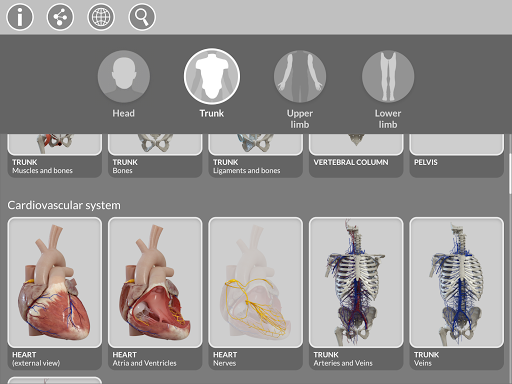

يسهل التقسيم حسب المناطق والمناظر المحددة مسبقًا مراقبة ودراسة الأجزاء الفردية أو مجموعات الأنظمة والعلاقات بين الأعضاء المختلفة.

نماذج تشريحية ثلاثية الأبعاد

• الجهاز العضلي الهيكلي

• الجهاز القلبي الوعائي

• الجهاز العصبي

• الجهاز التنفسي

• الجهاز الهضمي

• الجهاز البولي التناسلي (للذكور والإناث)

• الجهاز الصماء

• الجهاز الليمفاوي

• نظام العين والأذن